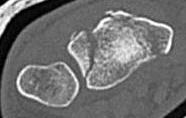

Distal Radius Angles

- radial volar tilt 11°

- radial inclination 22°

- radius is 11 mm longer than ulna

- ulna variance 2mm positive on average